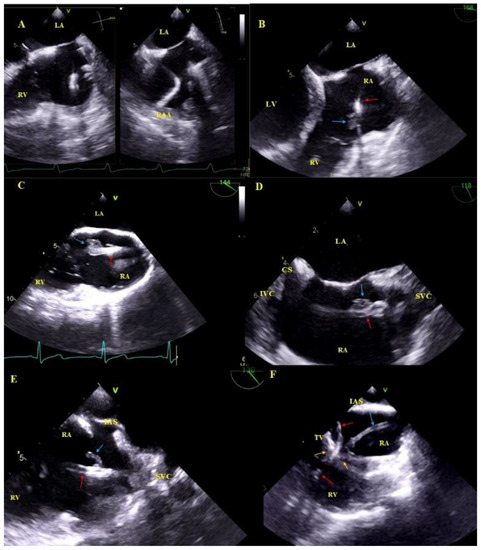

2.5. Echocardiographic Findings Associated with Endocardial Leads: Definition and Classification According to the Anatomy and Characteristic Features